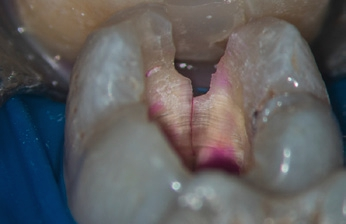

Eine genaue Evaluierung und Bestandsaufnahme kann in folgenden Schritten erfolgen: Die komplette Entfernung aller vorhandenen Restaurationen (Abb. 5) mit vollständiger Kariesexkavation (Abb. 6) ist in der Regel eine Voraussetzung. Es schließt sich die intrakoronale Befundaufnahme und Diagnostik (IKD) an, die Michael Arnold erstmalig didaktisch beschrieben hat [3]. Bei der IKD werden alle Informationen zusammengetragen, die diagnostisch unter dem Dentalmikroskop bereits vor dem Einsatz von Aufbereitungsinstrumenten erfasst werden können. Hierzu wird unmittelbar nach dem Anlegen der primären und sekundären Zugangskavität geprüft, ob alle Kanaleingänge dargestellt und sondiert werden können.

Wenn die Entscheidung für die Erhaltungsfähigkeit und eine endodontische Weiterbehandlung getroffen wurde, erfolgt die Ergänzung fehlender Zahnhartsubstanz – mindestens der fehlenden Zahnwände – durch einen präendodontischen Aufbau mittels Adhäsivtechnik (Abb. 10–14).